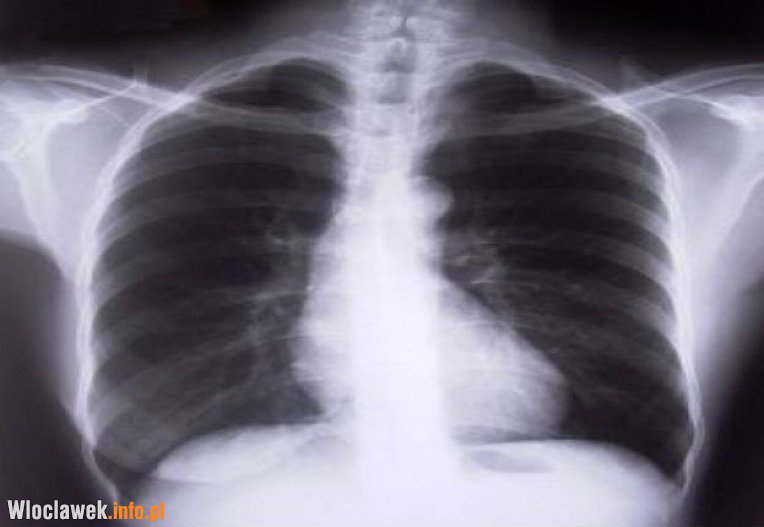

Przez trzy dni włocławianie mogą wziąć udział w bezpłatnych badaniach spirometrycznych, które mają kluczowe znaczenie we wczesnej diagnostyce chorób układu oddechowego. Z badań powinny skorzystać przede wszystkim nałogowi palacze.

Spirometria jest tak ważnym badaniem, jak pomiar ciśnienia tętniczego czy glukozy we krwi - podkreślają specjaliści z Polskiego Towarzystwa Chorób Płuc. Badanie spirometryczne trwa zaledwie 10 minut i jest bezbolesne, a jednocześnie pozwala wykryć niebezpieczne choroby układu oddechowego, takie jak POChP i astma. Palacze papierosów, którzy wcześniej nie mieli rozpoznanej POChP, powinni je wykonywać minimum raz na trzy lata.

Warto dodać, że wskazaniami do wykonania badania spirometrycznego są: uporczywy kaszel, zadyszka, duszność. Zlekceważenie tych objawów może grozić rozwojem poważnych chorób, takich jak np. Przewlekła Obturacyjna Choroba Płuc (POChP), na którą choruje około 2 mln Polaków.